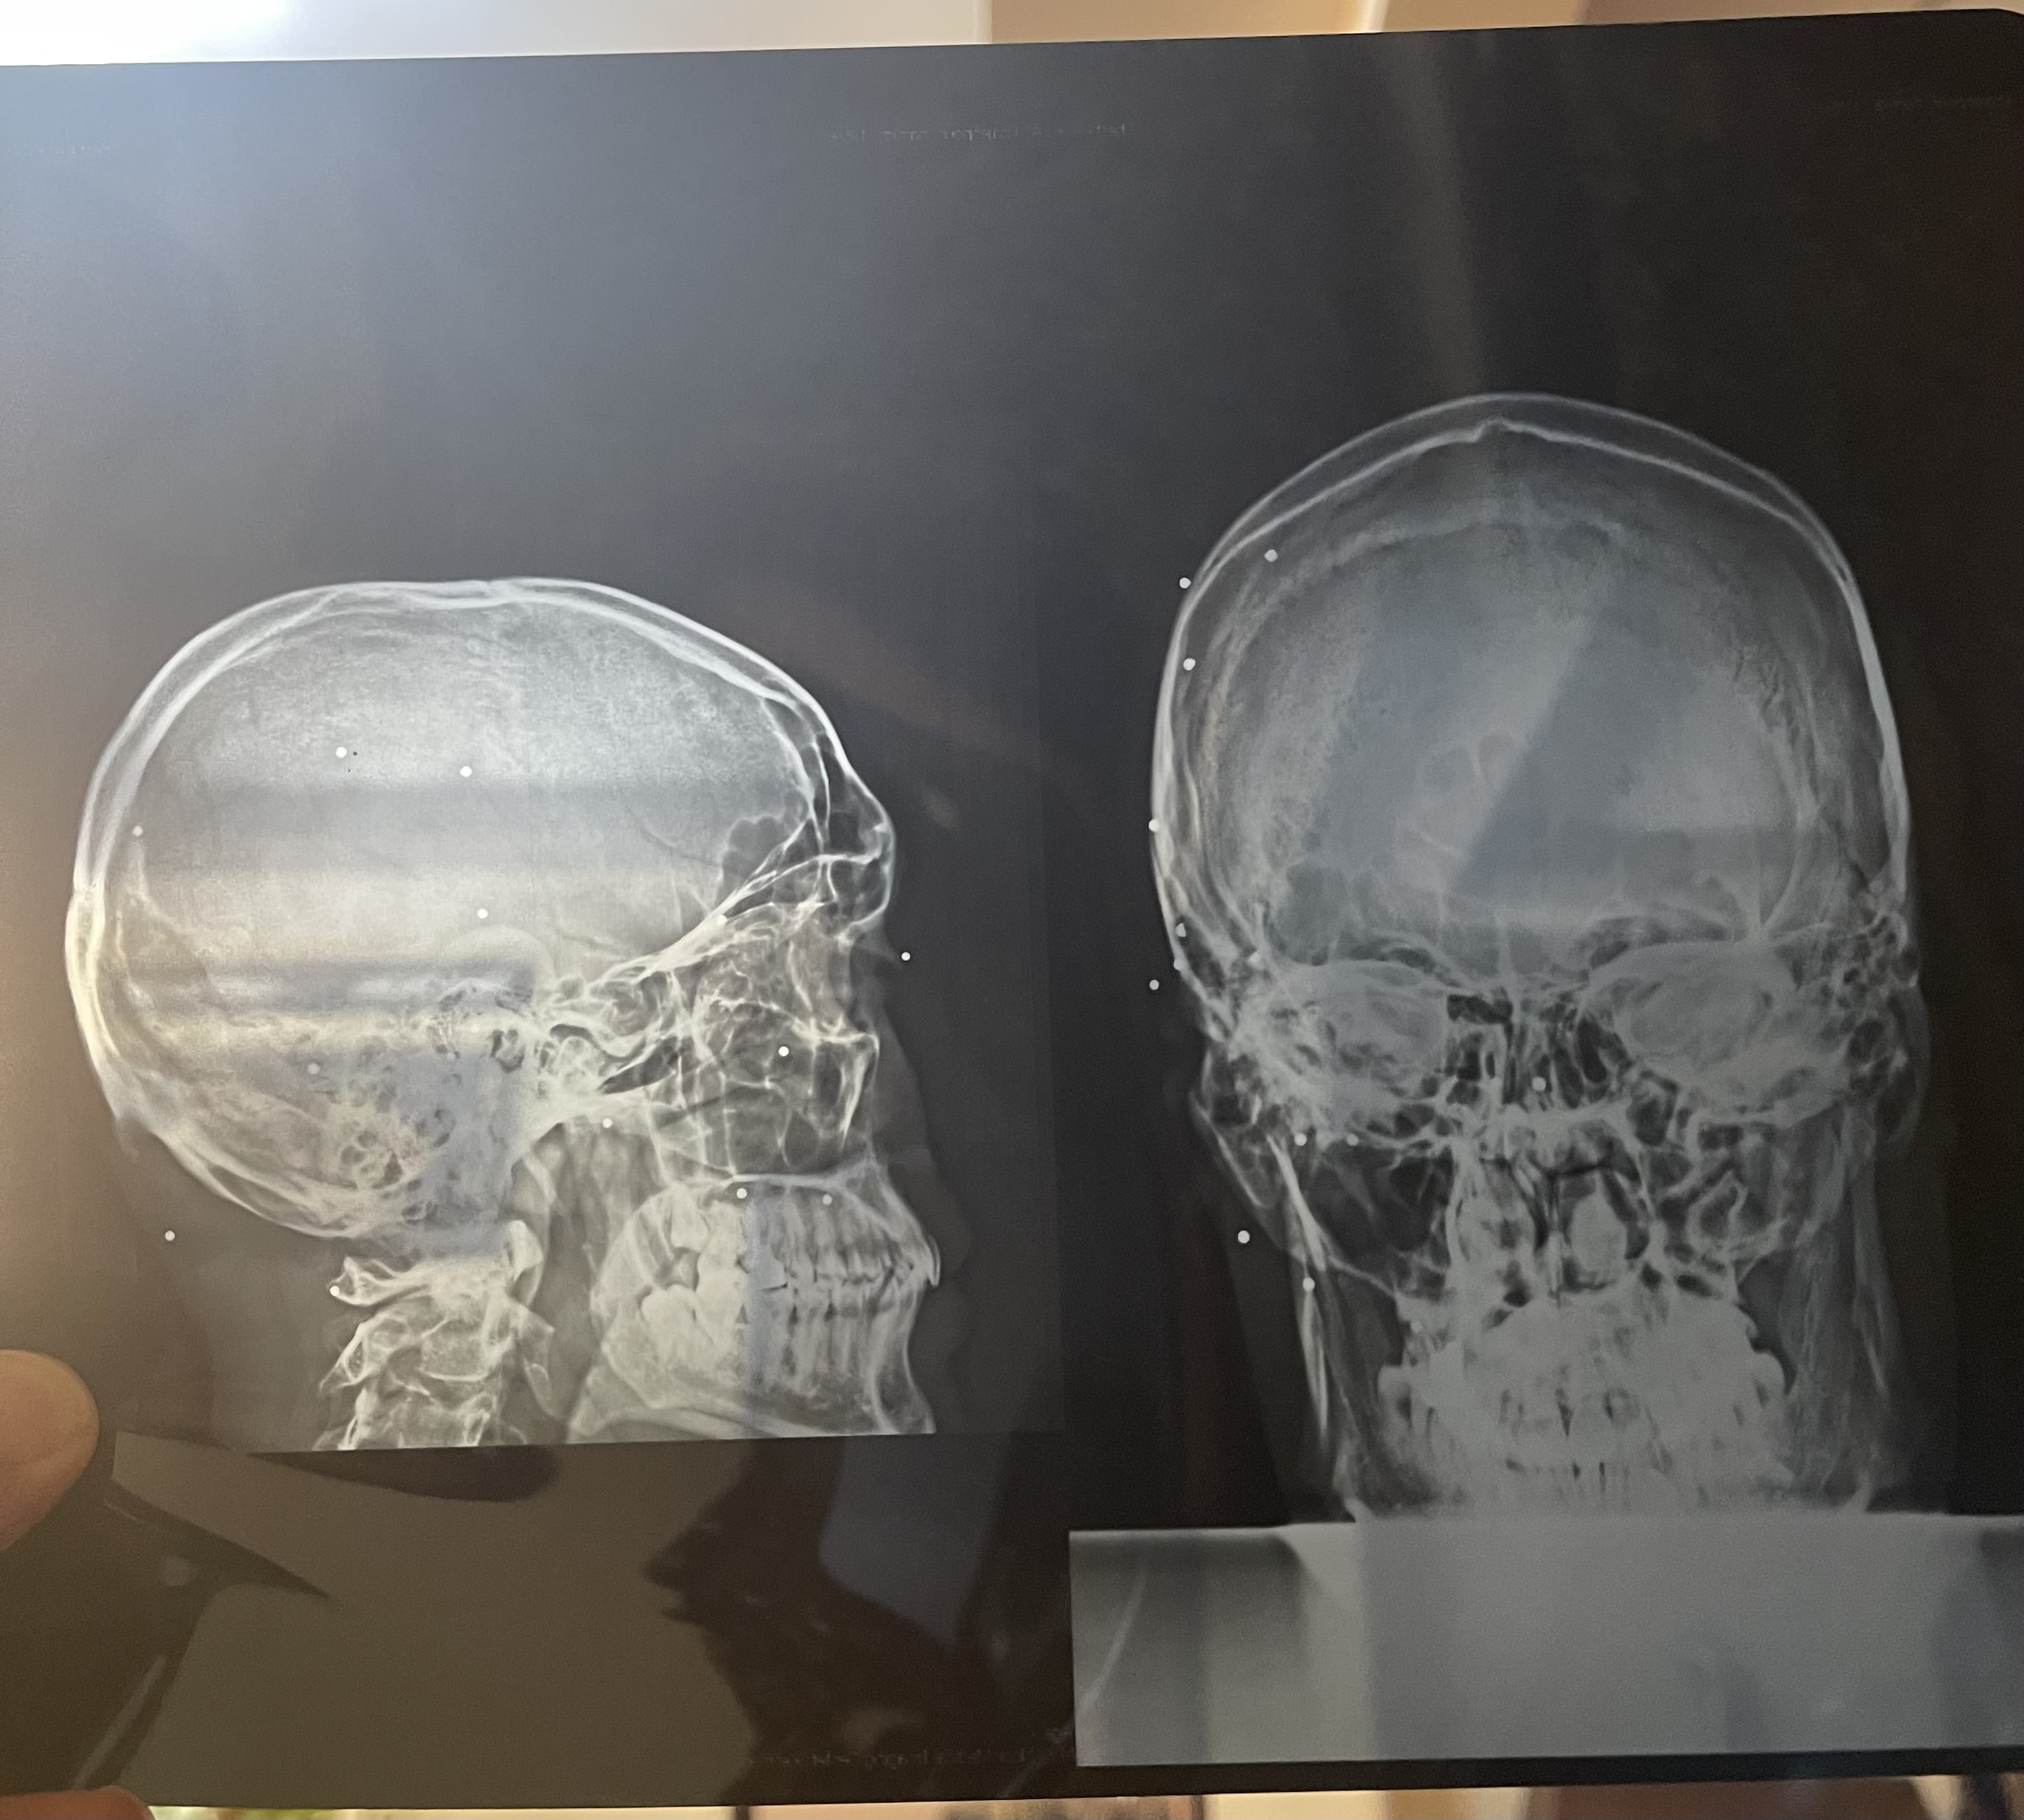

Hamid Reza was shot twice from a distance of about two meters with a pellet gun. One pellet goes right through his eye. Two pellets are implanted in his eye and his torso has so many that they’re difficult to count. In the immediate panic after being hit, Hamid Reza remembers screaming that he’s been blinded. He was holding his eyes shot in the shock. With the help of his friends, he managed to get to safety and they climbed into a car.

Hamid Reza was operated on that night and he left the hospital the next day for fear that it might to be safe to stay. He hasn’t sought follow up treatment for his eye which has no usable vision remaining. The rest of the pellets in his body, some were removed by a friend at Hamid Reza’s home. Eventually, they decided there were too many to try and remove them all.